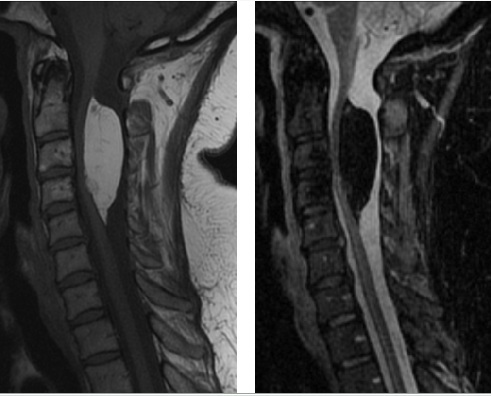

Seorang wanita 47 thn datang dengan parestesia di kedua lengan dan leher serta nyeri bahu sejak kecil. MRI tulang belakang cervcal menunjukkan (T1– left, STIR– right). Apakah diagnosis yg plg mungkin?

E. Lipoma

The correct answer is lipoma.

The MRI shows an intradural extramedullary mass which is fairly homogenous and is T1 hyperintense and STIR hypointense. The STIR sequence suppresses fat signal, suggesting that this mass is composed of fat. The other answer choices are lesions which are either not composed of fat or not found in the intradural extramedullary space.